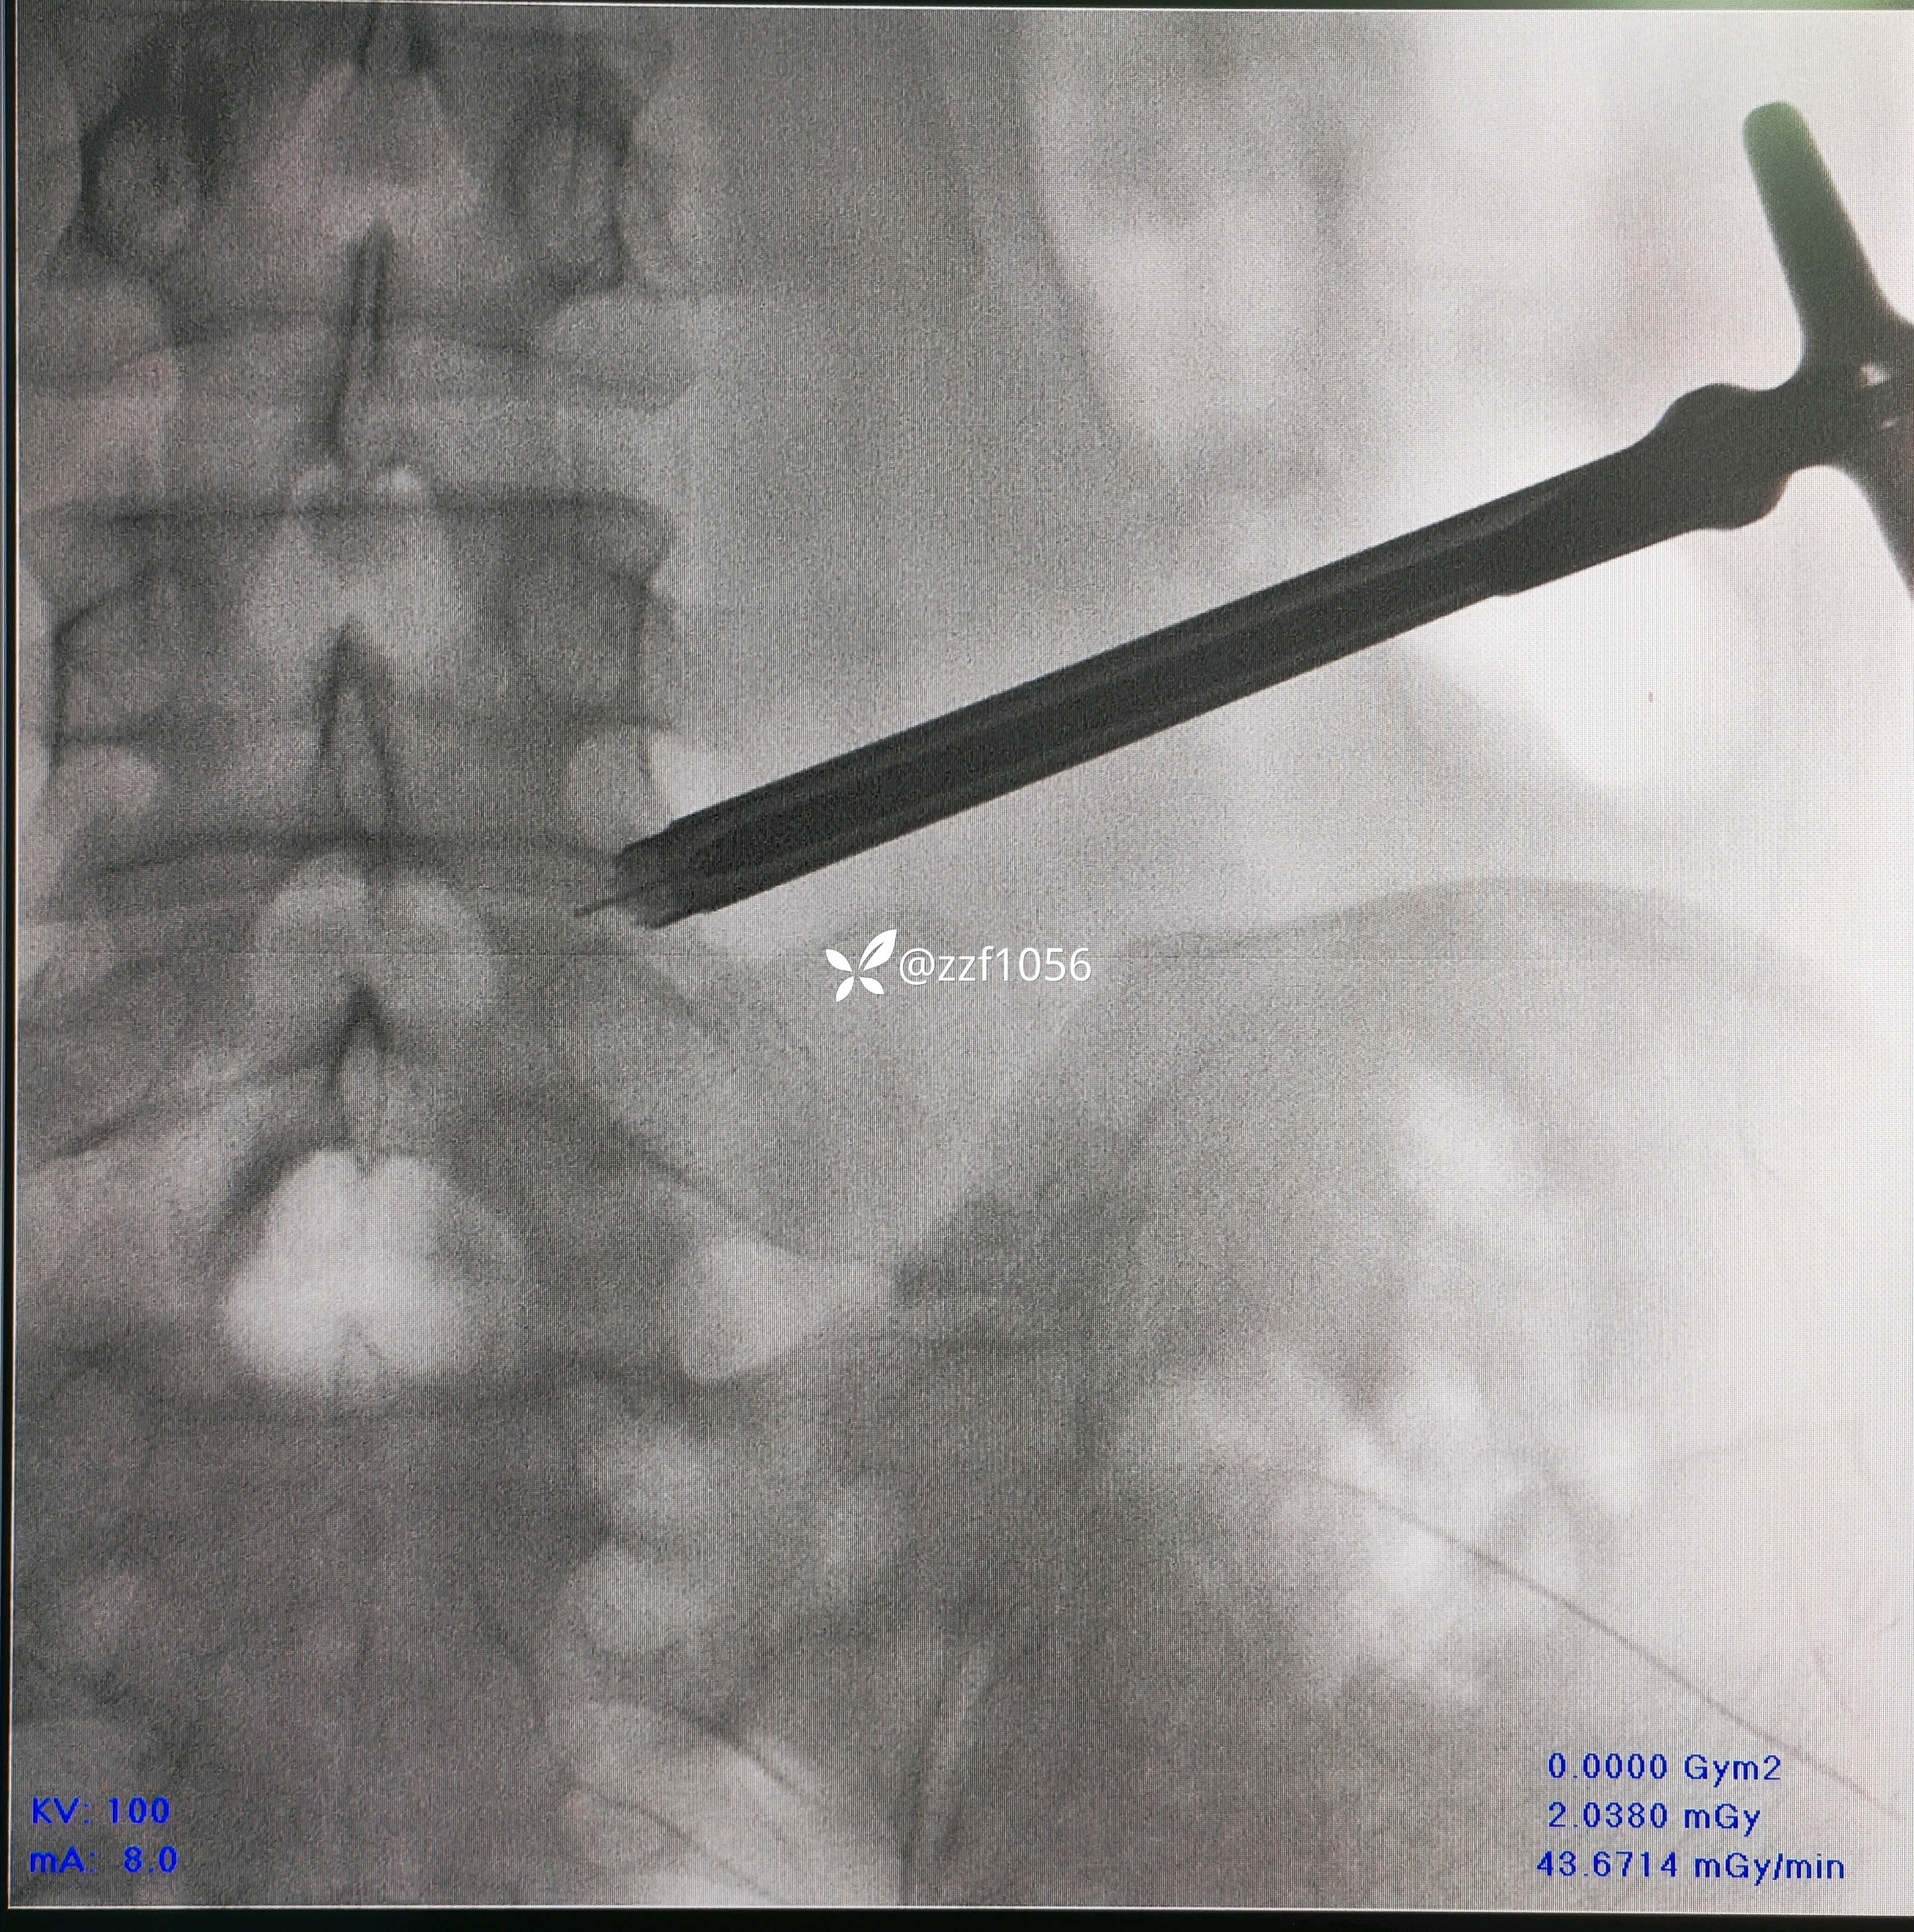

L4/5相对好穿刺

要求椎间孔处的手感

找关节缝的标志